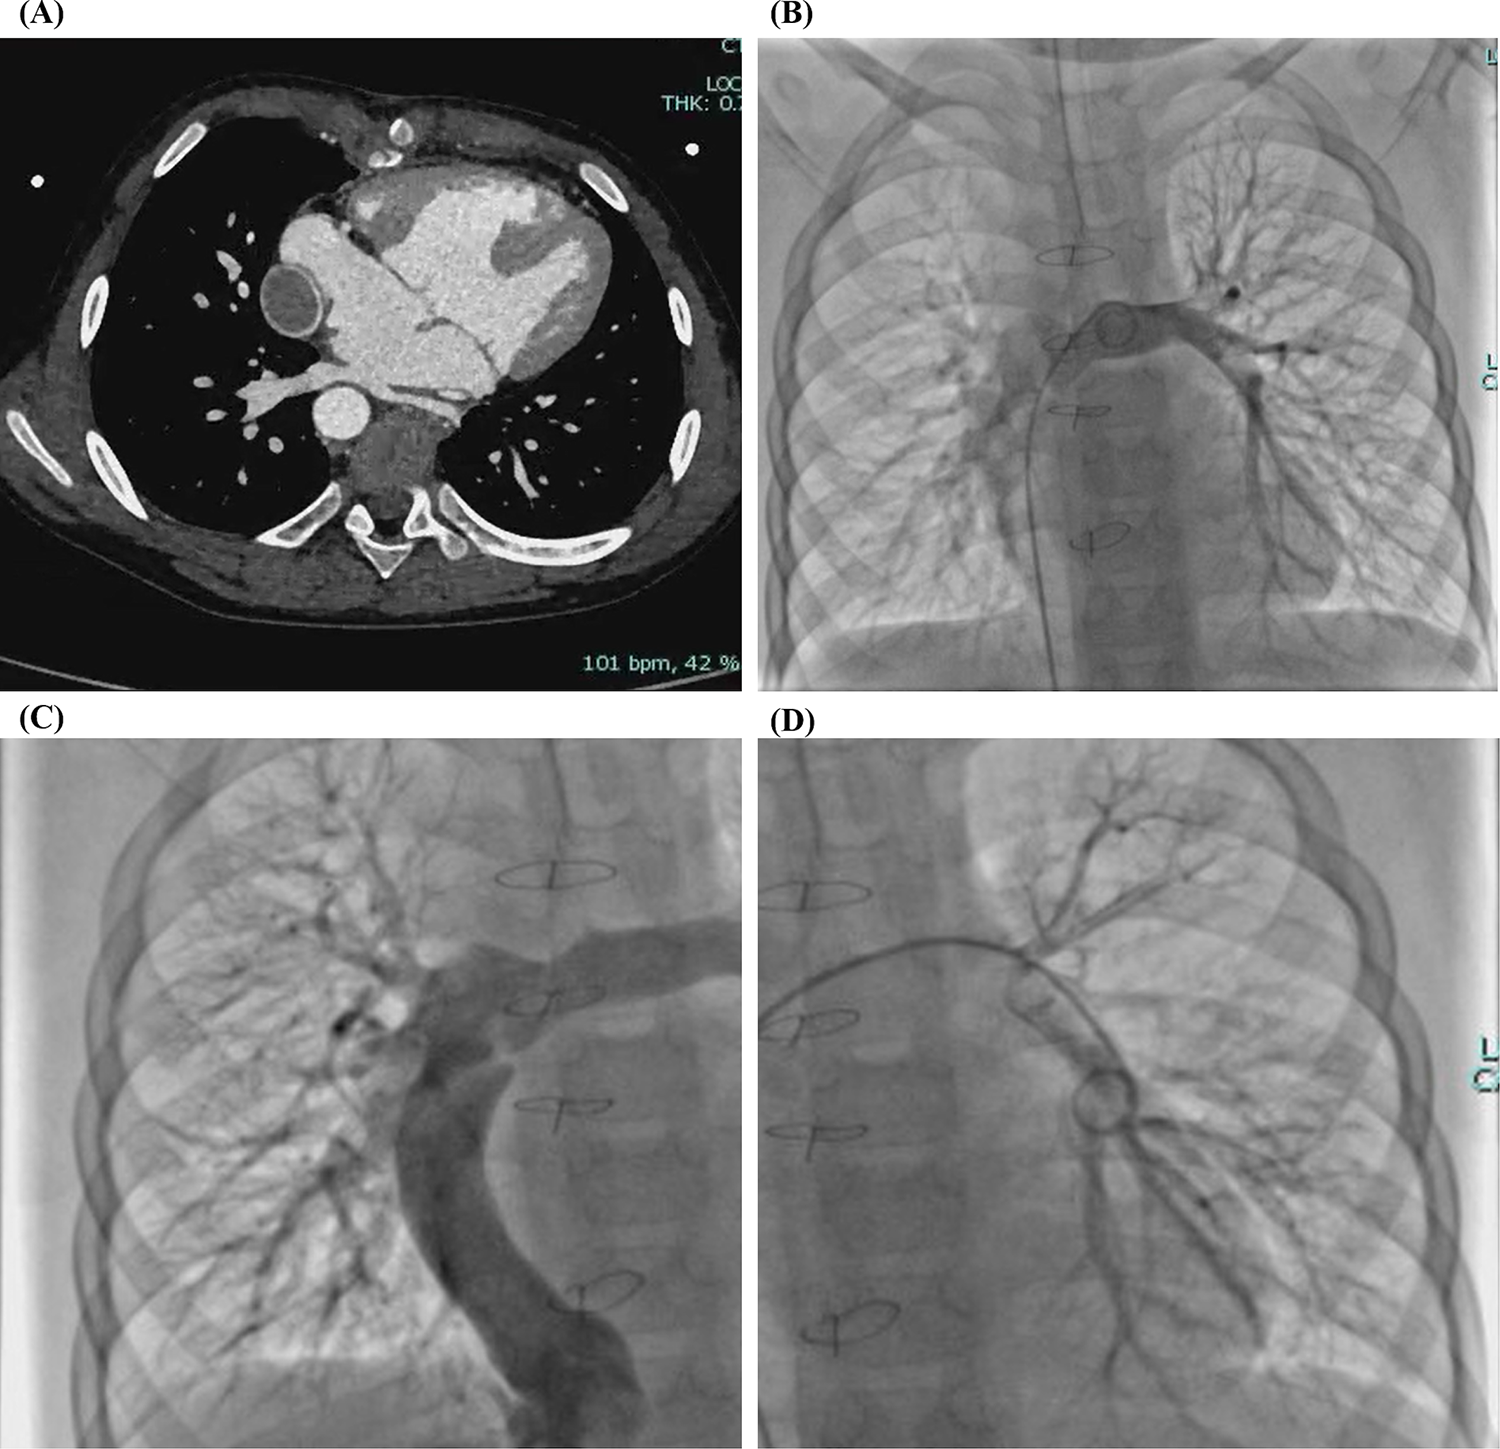

During a 3-year follow-up period, the SpO₂ gradually increased and stabilized at 97%–100% (Figure 3). Exercise tolerance improved markedly, the lips became pink, and digital clubbing resolved. Hemoglobin decreased to 127 g/L. Arterial blood gas analysis revealed a PaO₂ of 78.6 mmHg and an SO₂ of 95.8%. Contrast-enhanced cardiac CT demonstrated complete disappearance of the previously diffuse bilateral PAVMs (Figure 4A). Repeat cardiac catheterization confirmed unobstructed conduit flow and well-developed pulmonary vasculature. The previously extensive bilateral PAVMs had completely resolved, pulmonary circulation time returned to normal, and pulmonary artery pressures were 13/11/12 mmHg (Figure 4B–D).

Figure 4

(A) Contrast-enhanced cardiac CT after total cavopulmonary connection (TCPC) confirming complete disappearance of the bilateral diffuse pulmonary arteriovenous malformations (PAVMs). (B–D) Cardiac catheterization after TCPC demonstrating complete resolution of bilateral diffuse PAVMs.